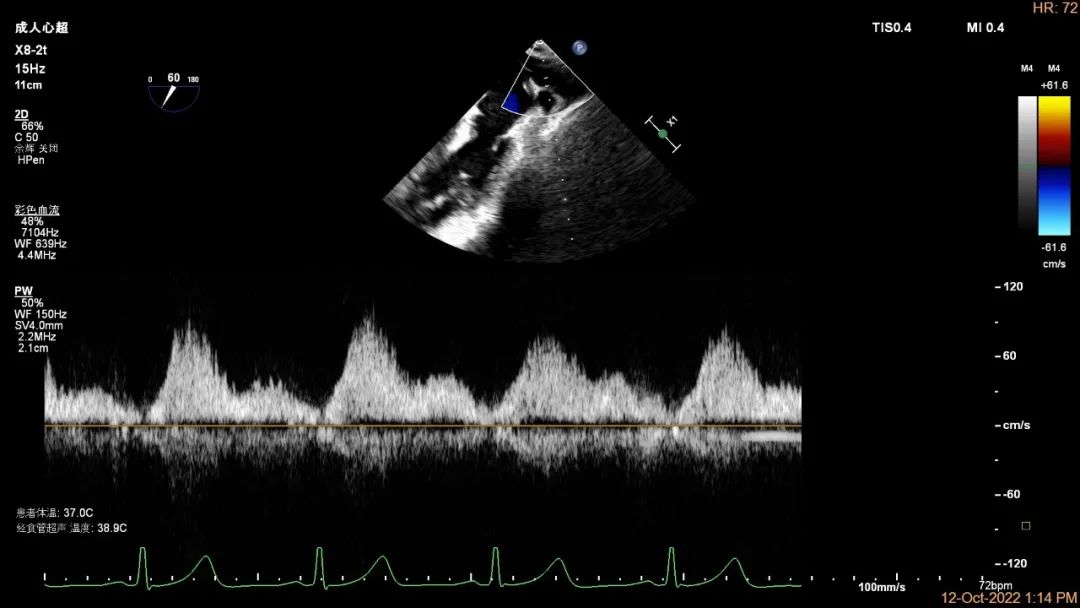

“贞”心一“课”|TEER成功治疗外交界隆起合并P3区宽大Flail病变一例

心血管内科博士,主治医师。专业: 心脏瓣膜病和心力衰竭,擅长危重心血管病患者治疗,冠心病、经导管微创瓣膜手术(TAVR、TEER)术前评估和围术期管理。发表国际期刊多篇。国际会议论文交流数次。